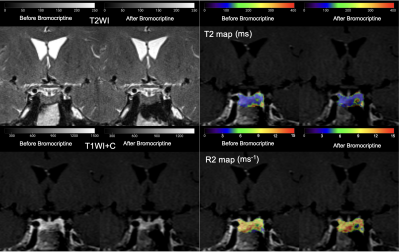

2383c812075c864cc005dca6b7f540cc.png

垂体催乳素瘤患者在接受多巴胺激动剂(DA)治疗前后,加速GRAPPA T2映射和传统MR序列的示意图。